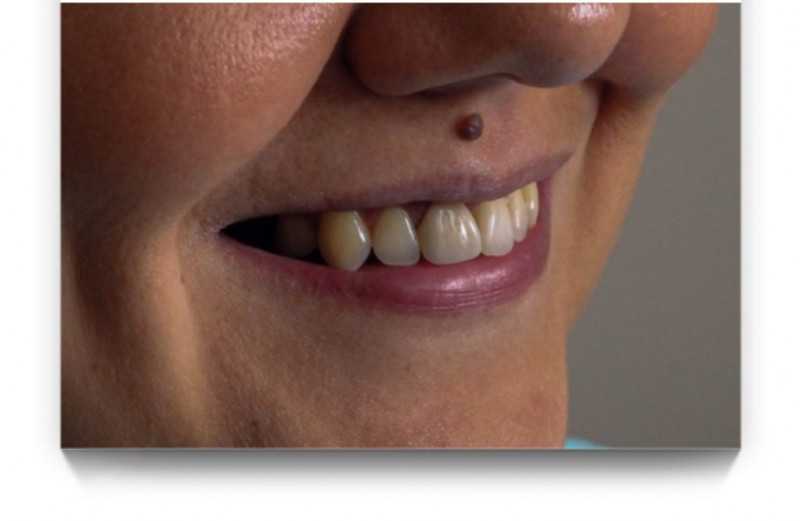

Установка коронки из диоксида циркония

Если сроки поджимают, а пациент хочет красивую улыбку— коронки из диоксида циркония беспроигрышный вариант. Компромиссная работа, так как имплантацию и ортодонтию пациент не рассматривал совсем. Длительное отсутствие нескольких зубов, в том числе переднего, хотелось восстановить в короткие сроки.

Доктор: Хухуа Георгий Амеранович